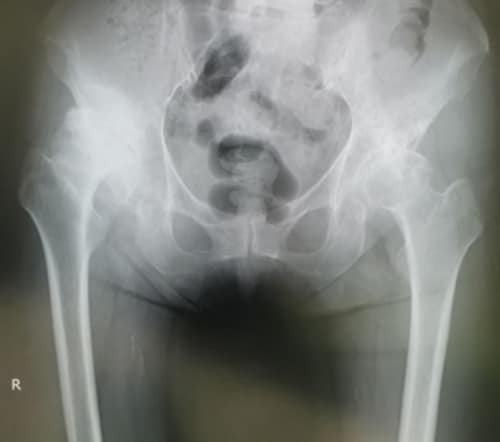

術後3ヵ月間は1〜2週間おきに通院していただき、人工関節の様子を確認しながらリハビリを行っていました。その後は1ヵ月に1度のペースとなり、現在では1年に1度、検診を受けていただいています。現在レントゲンとCT検査を行っても何も異常は見つからず、緩みなどもありません。